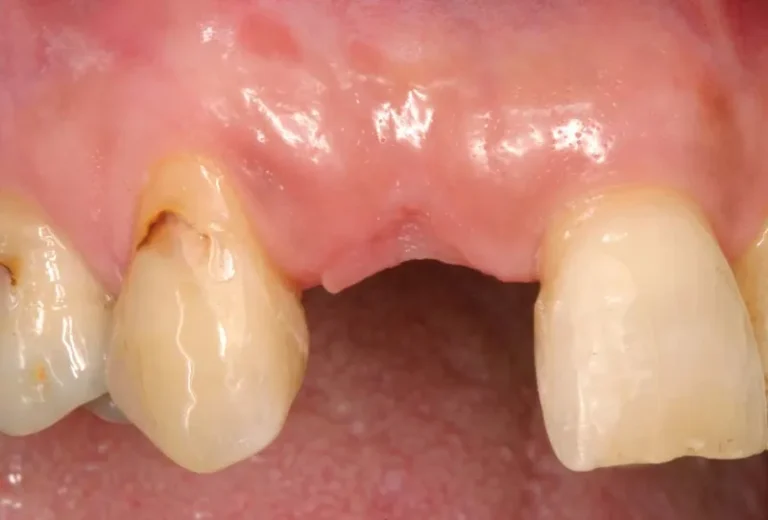

La regeneración ósea es un procedimiento quirúrgico fundamental en implantología dental que permite recuperar el volumen y la densidad del hueso maxilar o mandibular cuando este se ha perdido. Este tratamiento se vuelve necesario cuando el paciente no dispone de suficiente tejido óseo para sostener un implante dental de manera segura y estable. Mediante el…

La osteointegración es el proceso biológico fundamental que determina el éxito de los implantes dentales. Durante este fenómeno, el hueso del maxilar crece y se fusiona directamente con la superficie del implante de titanio, creando una conexión estructural y funcional que garantiza la estabilidad a largo plazo. Este proceso, descubierto por el profesor Per-Ingvar Brånemark…

La sanación de un implante dental es un proceso gradual que varía según cada paciente. Generalmente, la integración completa del implante con el hueso (osteointegración) tarda entre 3 y 6 meses, aunque la recuperación inicial de los tejidos blandos ocurre en las primeras semanas. Durante este período, es fundamental seguir las indicaciones del especialista para…